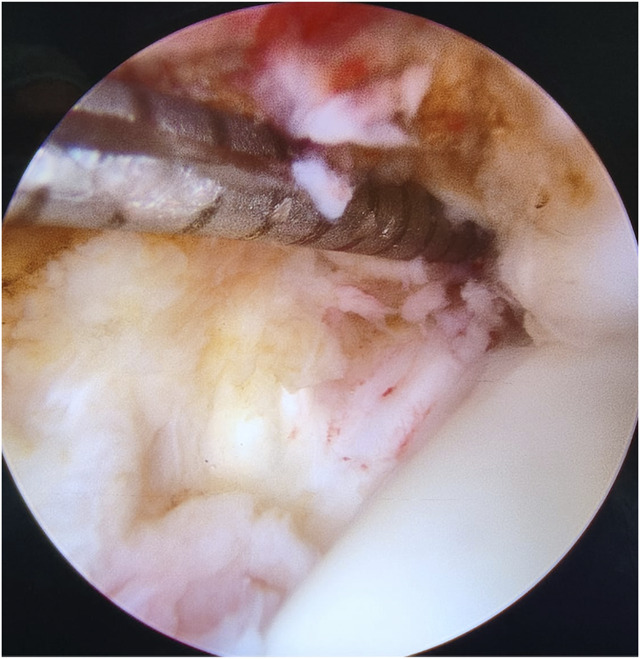

Background: Ankle injuries, often involving the syndesmotic complex, are common and may lead to acute instability. The syndesmosis, comprising several key ligaments, provides critical support for ankle function. This study assesses the efficacy and safety of the suture button system for isolated syndesmotic injuries, a treatment method that is gaining popularity over traditional transsyndesmotic screws.

Methods: A retrospective review was conducted on patients treated surgically with the suture button system for isolated syndesmotic injuries from January 2018 to December 2023. Key outcomes measured included time to full weight-bearing, returning of daily activities, and complications. The study also compared these outcomes with historical data from screw fixation methods.

Results: Thirty-two patients (20 men, 12 women; mean age 41.66 ± 16.57 years [range 16-72 years]) were analyzed over an average follow-up of 9.94 ± 5.49 months (range 3-28 months). Patients achieved full weight-bearing at 1.23 ± 0.31 months postoperatively, resumed daily activities with restrictions at 3 ± 1.09 months, and without restrictions at 6.67 ± 2.55 months. No major complications were reported; minor complications included implant removal due to irritation in two patients (6.25%) and minor wound issues in one patient (3.13%).

Conclusion: The suture button system demonstrated good outcomes in allowing physiological motion, low malreduction rates, and minimizing reoperation needs. The present results indicate a promising safety profile and functional recovery, despite limitations such as small sample size and lack of patient-reported outcome measures.